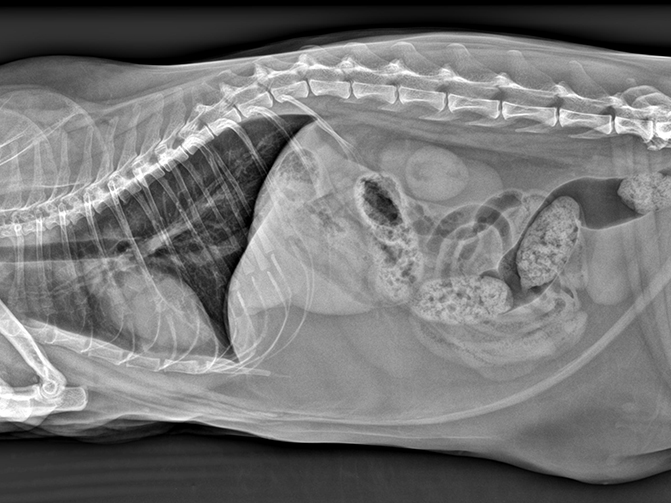

微焦点球管、微像素平板探测器以及高级图像处理算法是获取优越图像的黄金搭档,实现精准成像,提高病灶检出率。

舒博尔XVIEW-体化图像采集处理软件,具有强大的图像算法处理能力和人性化的操作流程,从登记-拍摄部位选择、采集处理图像、报告打印输出一气呵成,智能的动物解剖部位预设程序,可以根据动物类型、部位、体型自动调出高压曝光参数,使曝光参数的选取变得非常简单。图像处理算法根据不同的动物的组织密度差异进行了细分处理,确保各种动物拍摄均能获取优异的图像质量,专业的辅助诊断测量。I具包含VHS (脊柱心脏评分)等,极大的帮助医生进行病患诊断。